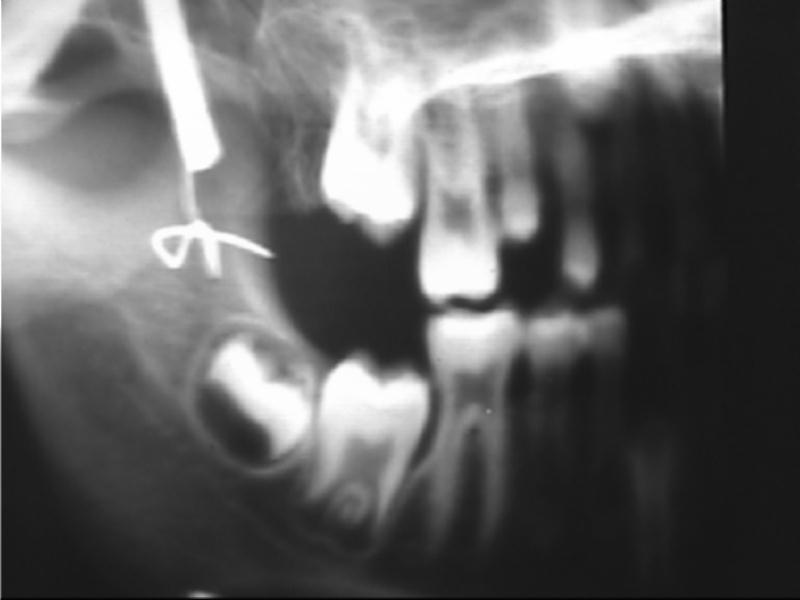

Xương sọ vùng hàm trên và dưới trẻ 9 tuổi. Từ trái qua phải là răng số 6 v v, số 5,4 sữa |

Xương sọ vùng hàm trên và dưới trẻ 9 tháng tuổi |